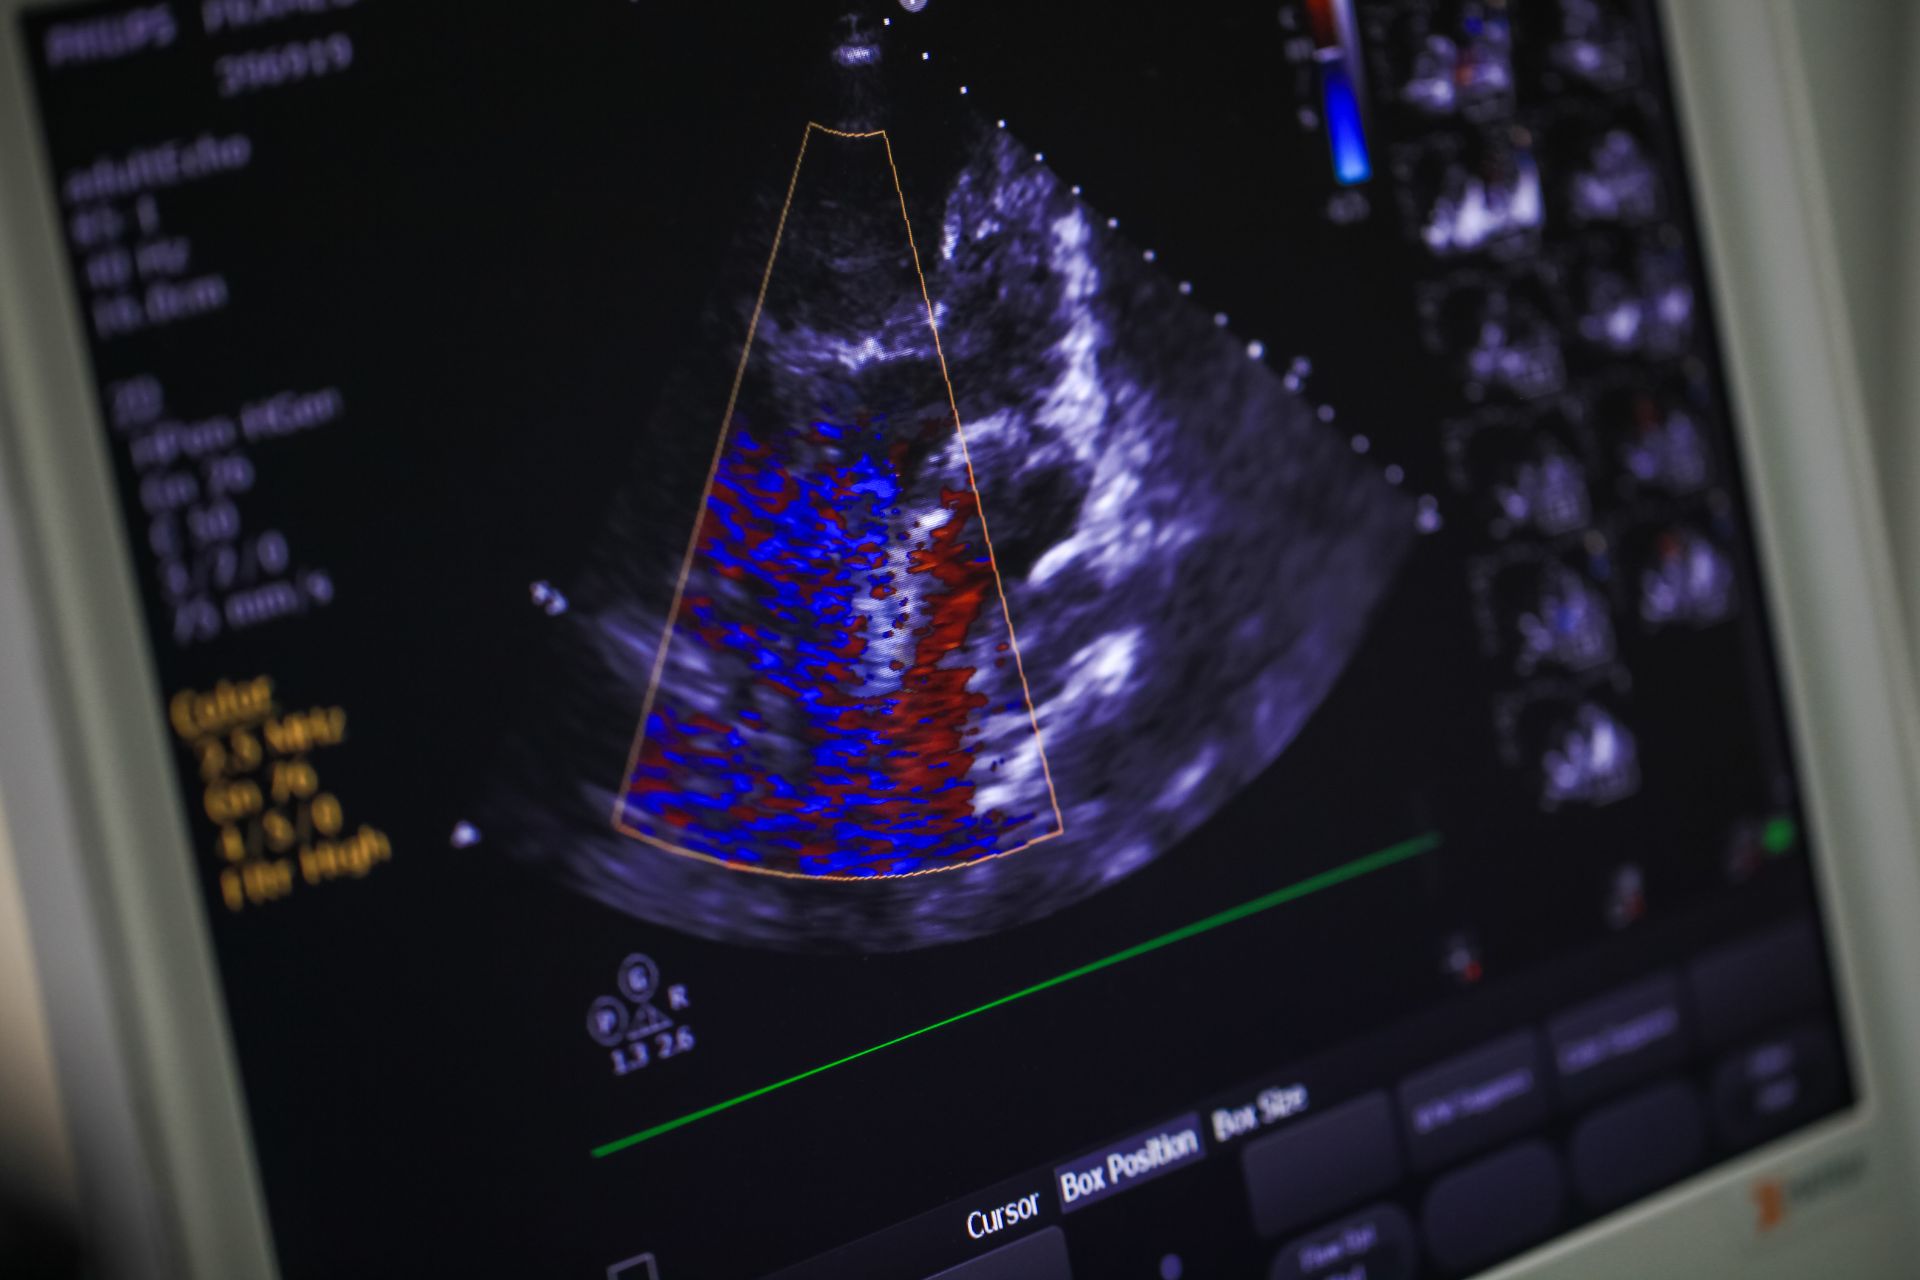

An echocardiogram is a non-invasive test that uses sound waves to produce live images of the heart, allowing doctors to monitor how the heart and its valves are functioning. This test provides information about the size and shape of the heart, as well as its pumping capacity. A physician may recommend an echocardiogram to investigate signs or symptoms of heart problems, and it can help diagnose and monitor certain heart conditions over time. The information gathered from an echocardiogram helps determine the next steps in a patient’s treatment plan.

An echocardiogram uses a device called a transducer. This instrument sends high-frequency sound waves through your chest toward your heart. The sound waves bounce, or “echo,” off the heart’s structures, and the transducer picks up the returning waves.

A computer then converts these sound waves into moving images, which are displayed on a monitor, allowing the cardiologist to see the heart beating and pumping blood. Different types of echocardiograms exist, including transthoracic, transesophageal, and stress echocardiograms. Each type offers a distinct perspective on the heart.